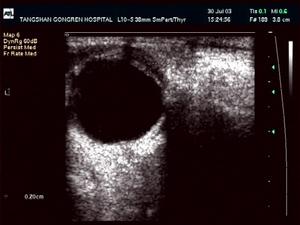

2.B超探查 在診斷脈絡膜脫離上的作用尤其突出,它不但可明確定出脫離的部位,還可根據脈絡膜上腔為低密度或高密度來區分是滲出性脫離或者出血性脫離。此外尚可顯示有無眼內占位以及視網膜脫離等伴隨情況。

5.影像學檢查 UBM CT和MRI均有助於脈絡膜脫離的診斷與鑑別診斷。